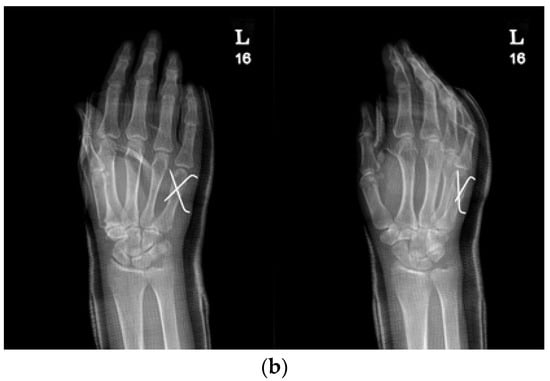

2.3. Surgical Technique